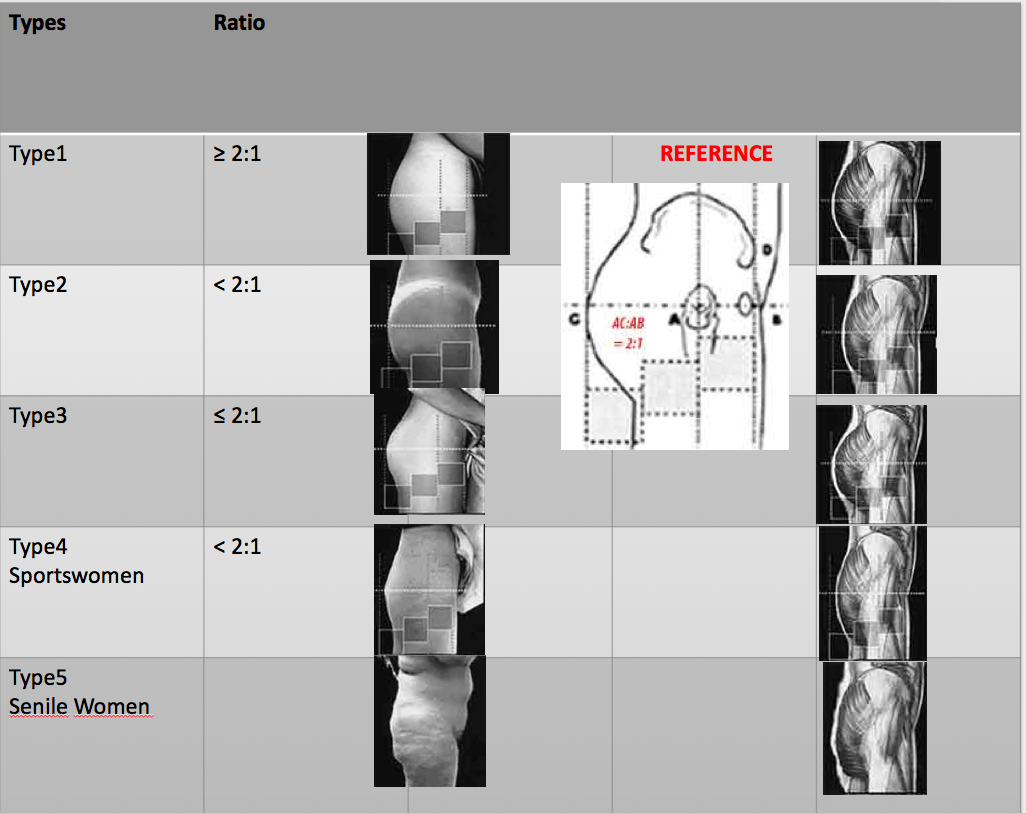

Anthropometric Analysis of Gluteal Projection

Perfect Ratio AC:AB =2.1 is the ,, best,, ratio for the study of gluteal projection among white caucasian female butts .

The 5 types

in function of the ratio AC:AB